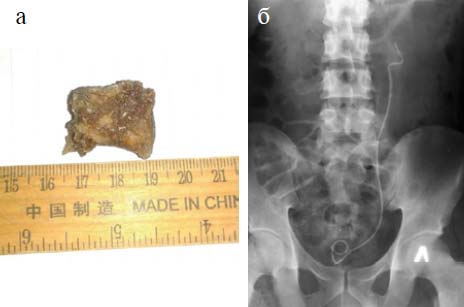

Из почки удалён камень размером 3,0×2,5 см, а из нижней группы чашек вымыванием удалено множество мелких камней (рис. 3).

Рис. 3. Пациент Г.С.: а — камень, удалённый из почки; б — обзорная урограмма после операции, в левой почке не обнаружена тень камня